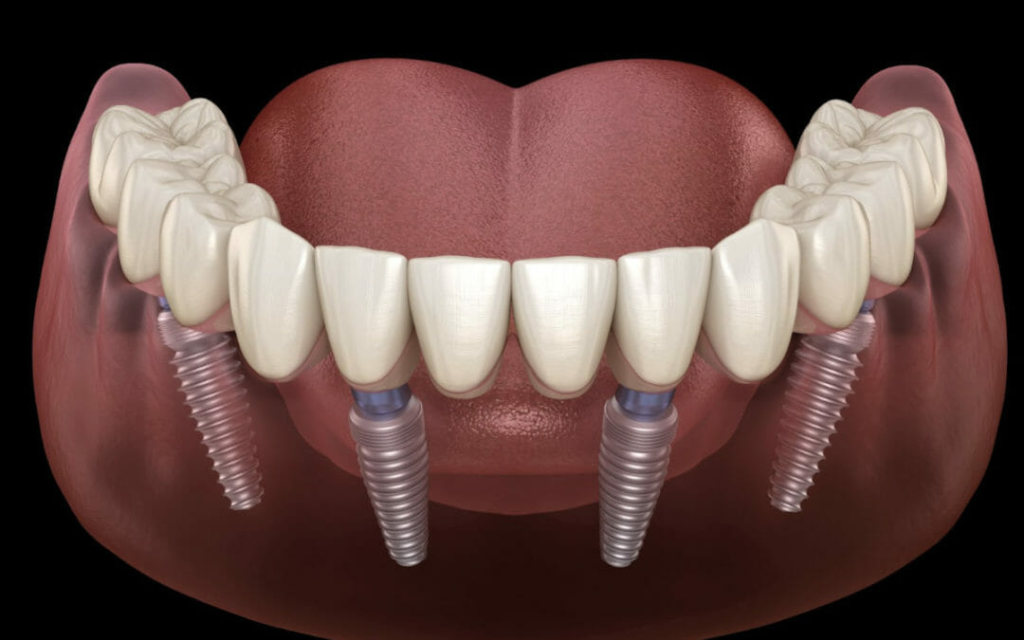

Implant guided dentures, also known as implant supported dentures, are a type of overdenture that is securely anchored by dental implants. Unlike conventional dentures, which rest on the gums and may shift or cause discomfort, these dentures lock into implants placed in your jawbone for increased stability and support.

They combine the benefits of fixed implants and removable dentures, providing better functionality, comfort, and aesthetics.

- Initial Consultation & 3D Imaging

A thorough examination and digital scans are done to assess your jawbone and create a personalized treatment plan. - Implant Placement

Titanium implants are surgically inserted into the jawbone. These serve as artificial tooth roots. - Healing Period (Osseointegration)

Over the next 3–6 months, the implants fuse with your bone, creating a strong and stable foundation. - Denture Attachment

Once healed, a custom-made denture is designed to fit precisely over the implants. Depending on your case, this can be:- Fixed (permanent)

- Removable (snap-on)

Usually 2–6 implants per arch are needed, depending on your bone density and the type of denture.